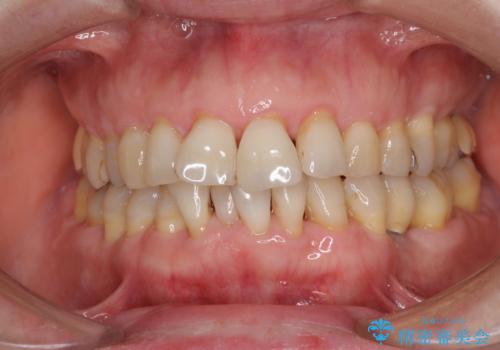

口元の出っ張りとデコボコを改善したい

- 近医にてインプラント治療を行った後に矯正治療を希望され、来院された患者様です。

口元の突出感とデコボコが気になっているとのことでしたが、インプラントが既に3本埋入されていたため、抜歯矯正による口元を引っ込めることができない状況でした。

近医での歯周病治療の影響でブラックトライアングルが発現していたため、IPR(歯と歯の間を削る)で隙間を改善しつつ、インプラントを固定源に歯列全体を後方へ移動させることとしました。